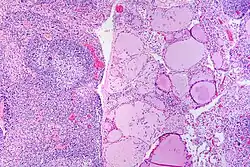

![]() |

Hashimoto's thyroiditis | Hashimoto's thyroiditis with lymphoid infiltration. | Category: Hashimoto's thyroiditis with lymphoid infiltration | Hashimoto's thyroiditis |